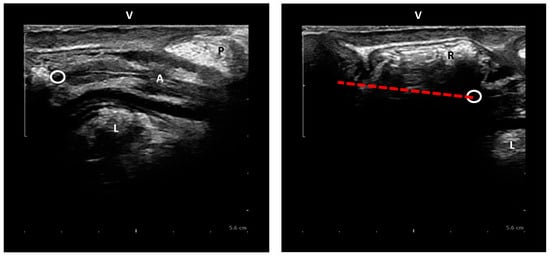

2.4. Imaging Analysis

Figure 4. Dynamic perineal descent on EVUS (red dashed): i.e., difference in movement of the ARJ between rest and maximum Valsalva. P = perineal body, L = Levator ani muscle, A = Anal canal, R = Rectum, V = Vagina, circle = ARJ.